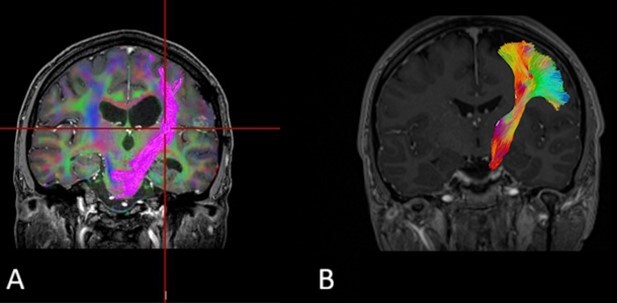

Diffusion tensor-based tractography enables non-invasive reconstruction of white matter pathways in the human brain using two main algorithms: deterministic and probabilistic. Deterministic tractography generates white matter filaments that follow the dominant diffusion direction in individual voxels, providing fast but imprecise reconstruction; however, it is limited in areas with crossed filaments. Probabilistic tractography, on the other hand, models uncertainty and allows for more accurate mapping of complex neural connections, although it is computationally demanding and more difficult to interpret. This article discusses the theoretical foundations, strengths and weaknesses, and clinical applications of both approaches, with particular emphasis on their application in neurosurgery and neuroradiology.